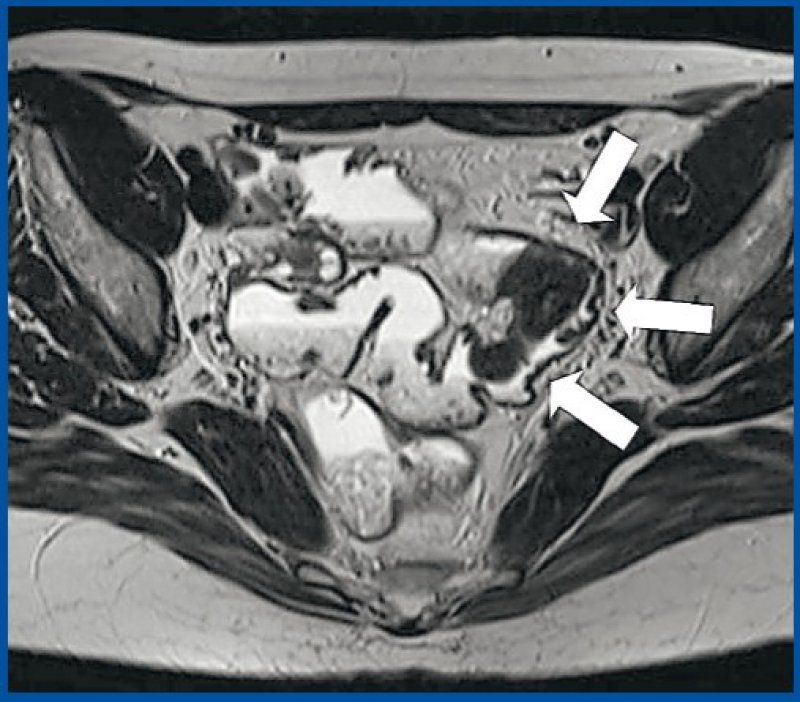

Absence of gas in rectum. Apposed inner walls of sigmoid colon pointing toward pelvis. colon sigmoideum und linker distaler ureter (1). I tyndtarmen bliver madens næringsstoffer spaltet og optaget sammen med cirka ni liter væske. Its complexity is rooted in embryonic development and the intestinal rotation that occurs during that time. Sessile polyp are cells that grow inside your colon lining. Staging colon and sigmoid cancer by ct and mri. Esovitý tračník, esovitá klička tračníku, též sygmoid colon a pelvic colon. 90 cc grade 3 toxicity could reduce from 26.7 to 5.4%. Sigmoid, sigmoid colon, sigmoidocolic, colon sigmoid, colon, sigmoid. Die intestinale endometriose führte bei 4 patientinnen zur stenose und bei einer zu rectalen blutungen. Přechází z colon descendens kaudálně → kraniálně a mediálně přes okraj malé pánve. What are synonyms for colon, sigmoid?